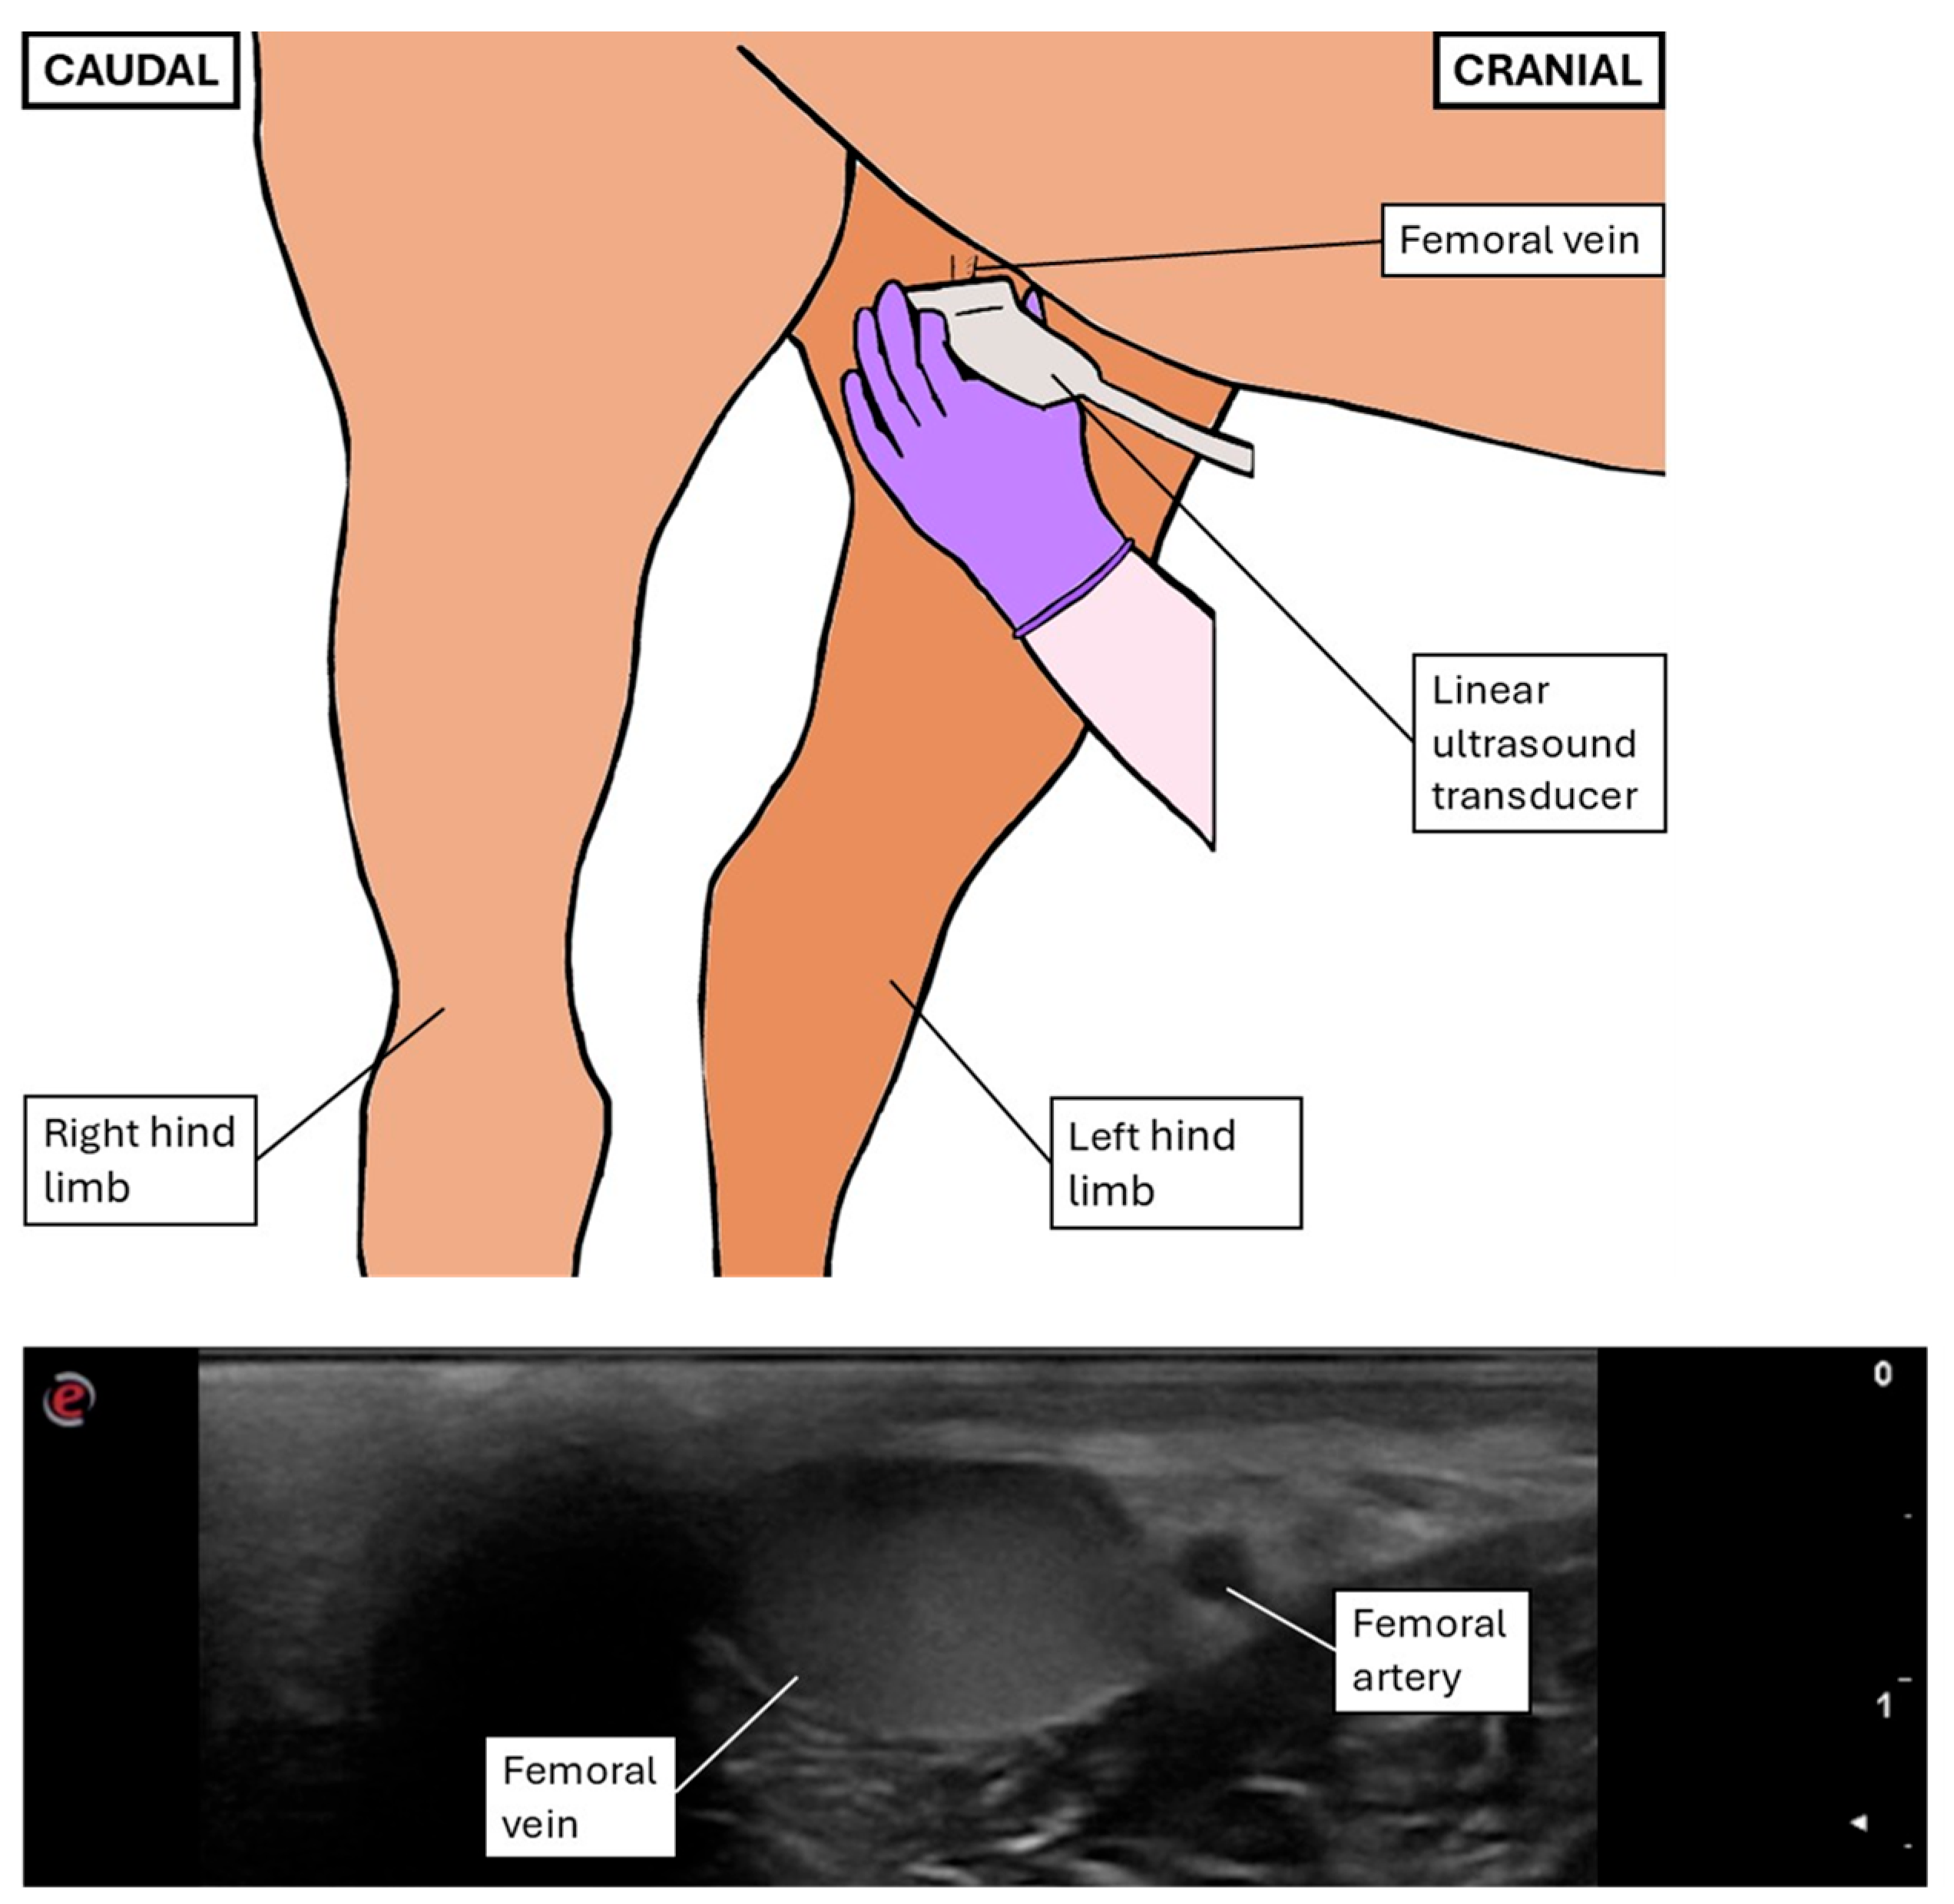

2.3. Ultrasonographic Measurements and Indexes Performed After Image Acquisition

2.3.1. General Variables

2.3.2. Transrectal Variables

2.3.3. Inguinal Variables